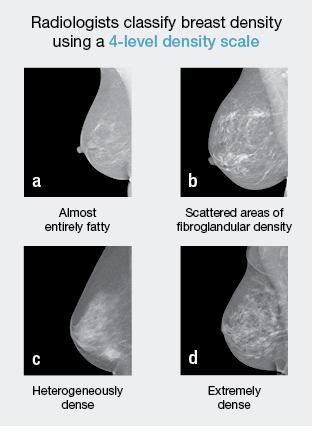

There are 4 levels of Breast Density –

40% of women have Dense Breasts. A Mammogram is the only way to determine and measure Breast Density. When you have a Mammogram, the radiologist reading it knows if you have Dense Breasts. You should ask for a copy of your radiology Mammogram report and ask if your breasts are dense.

In Dense Breasts the reliability of screening mammograms can be reduced by as much as 50%. Breast Density shows as white on a Mammogram and Cancer also shows as white, therefore Cancer tumours can be masked and obscured and may remain unseen on a screening Mammogram.